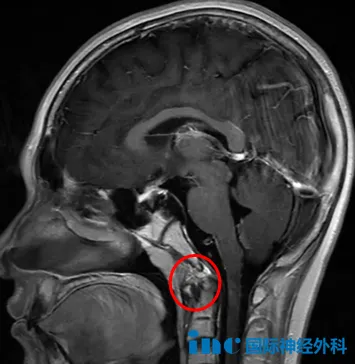

更为不幸的是,今年小海的头痛症状突然加重。这次检查终于揭示了脑瘤的真实情况——颅底斜坡区存在一个33×26×33mm的大型肿瘤,已经侵犯左侧海绵窦区域,导致垂体移位,连垂体柄都被推挤变形。医生高度怀疑这是脊索瘤。

当得知小海可能罹患脊索瘤时,父母的心情顿时沉重。这是一种手术全切极其困难、复发率较高、手术风险显著的罕见肿瘤。小海的肿瘤恰好位于斜坡区域,该位置处于颅底中央,紧邻脑干、基底动脉、颅神经、垂体及海绵窦等重要结构,关系到患儿的生命维持、神经功能、内分泌调节和传导等关键生理功能,任何手术损伤都可能引起严重神经功能障碍!

术后小海恢复状况持续良好。四个月后的随访中,福教授表示:"MRI检查结果非常理想,鼻腔结构完全正常,未见明显肿瘤残留征象。"